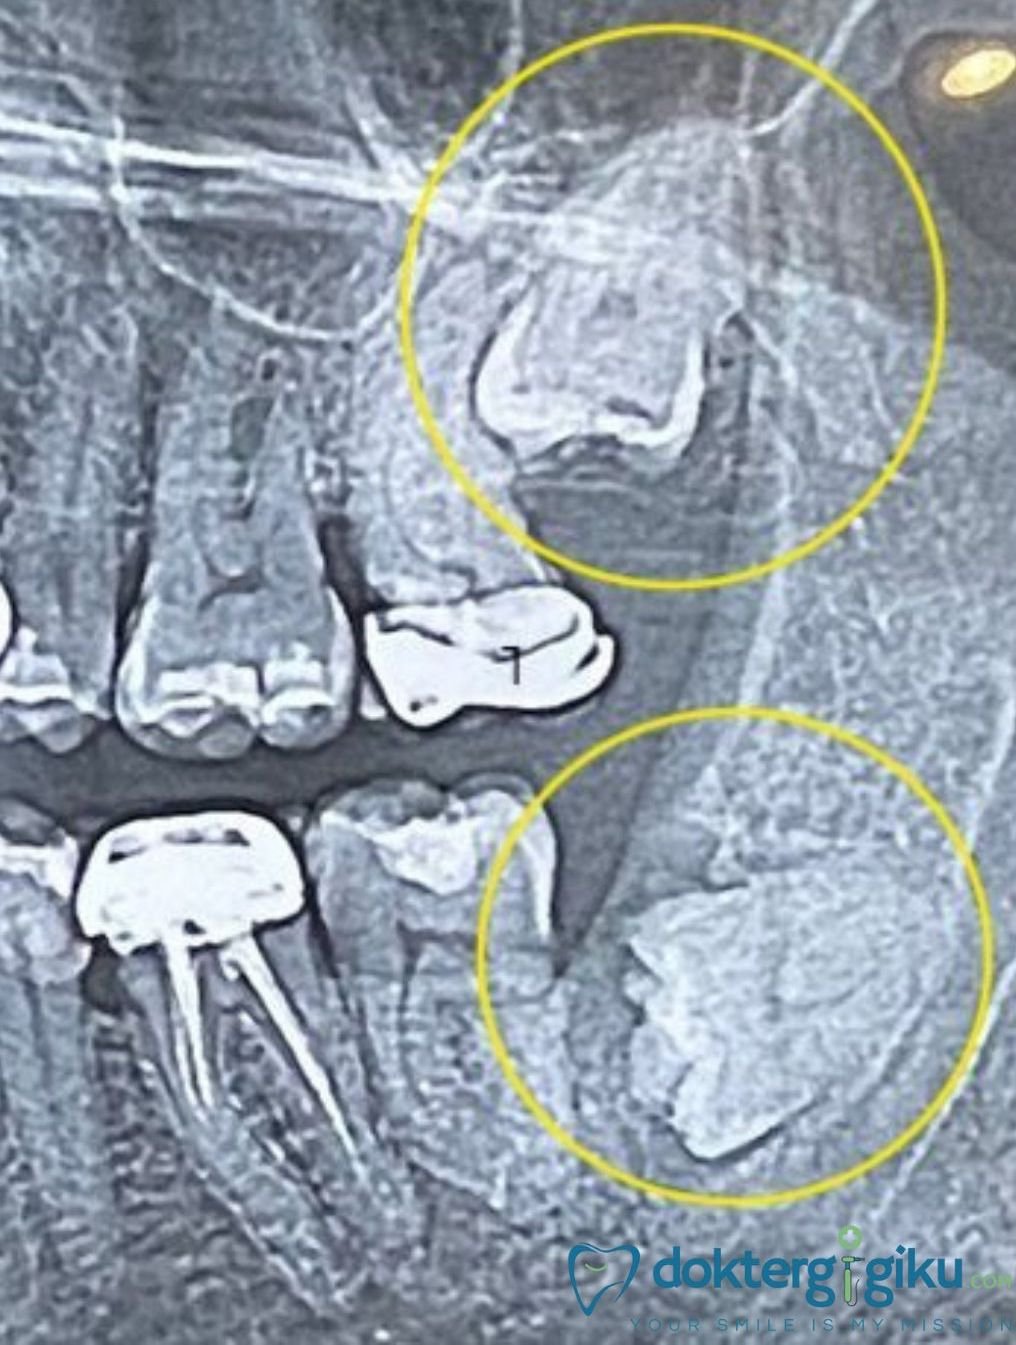

Rahang modern lebih kecil, membuat gigi bungsu sering terjebak di dalam tulang atau gusi (impaksi). Gigi impaksi bisa tumbuh miring, menekan gigi sebelahnya, atau tidak muncul sama sekali.

- Kista dan Komplikasi Lain

Dalam beberapa kasus, jaringan di sekitar gigi bungsu yang impaksi bisa membentuk kista atau tumor jinak yang merusak tulang rahang. Walaupun jarang, kondisi ini perlu diwaspadai.

📚 Rekomendasi klinis terbaru menekankan pentingnya evaluasi radiografi (rontgen panoramic) pada usia 17–21 tahun untuk menentukan apakah gigi bungsu perlu dicabut atau dipantau. (Ghaeminia et al., 2021, British Dental Journal)